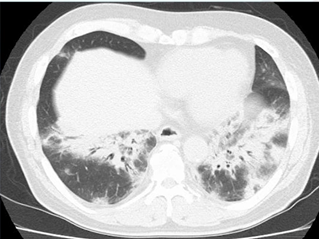

リバースドハローサイン(逆ハローサイン)とは、胸部CT画像で、中心に円形のすりガラス陰影があり、その周囲を三日月状または完全な輪状の浸潤影が取り囲んでいる画像所見です。この所見は、肺感染症や、非感染性の肺疾患(悪性腫瘍・膠原病・薬剤性)などのサインである可能性があり、早期の鑑別診断が必要です。

■CT所見

浸潤影を認め、その内部にすりガラス影を認める「リバースドハローサイン」です。器質化肺炎の時に出現すること多いです。入院管理になりますが、このような陰影を見た時には抗生剤投与を行い、起炎菌や反応をみながら「結核」や「悪性腫瘍」、「膠原病」、「薬剤性」の可能性を否定してから、PSL投与する事となります。